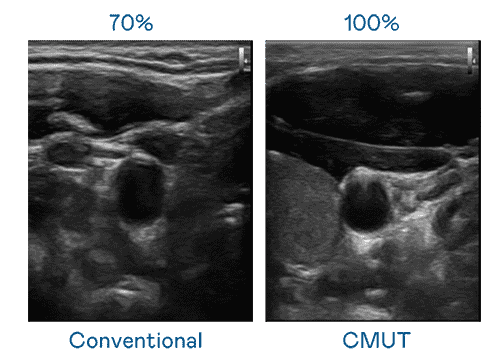

CMUT 技术是一种用电容式微机电元件来产生超音波讯号的技术。。。。与传统 PZT 压电式技术相比,,CMUT 频宽增加 30%,,,,更宽频的超音波讯号让影像解析度大幅提升,,,是实现高影像品质医疗超音波扫描、、、、促进精准医疗发展的关键技术。。。

大频宽带来超清晰影像

超音波影像的解析度高低,,首先取决于探头能发出的讯号频宽。。。。至成国际 CMUT 可提供高清晰的超音波讯号,,提供高频宽、、高灵敏度、、影像纹理细节更高的超音波影像,,,协助医护人员缩短影像判读时间及利用精准的医疗影像进行诊断。。。。